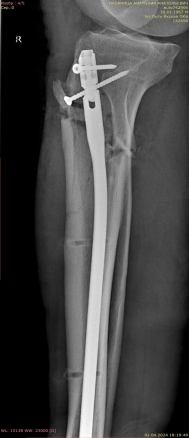

2) Мужчина, 57 лет. В результате падения бревна на область голени получил травму — открытый оскольчатый перелом верхней трети диафиза правой большеберцовой кости со смещением отломков (рис. 4).

Рис. 4.

Ввиду выраженного отечного синдрома в области перелома была выбрана методика конверсионного остеосинтеза, в экстренном порядке выполнены ПХО раны, фиксация перелома аппаратом внешней фиксации, назначена антибиотикотерапия (рис. 5).

Рис. 5.

После заживления раневого процесса и спадения отека на 12-е сутки выполнен закрытый блокируемый остеосинтез интрамедуллярным стержнем Expert внеочагово (рис. 6).

Рис. 6.